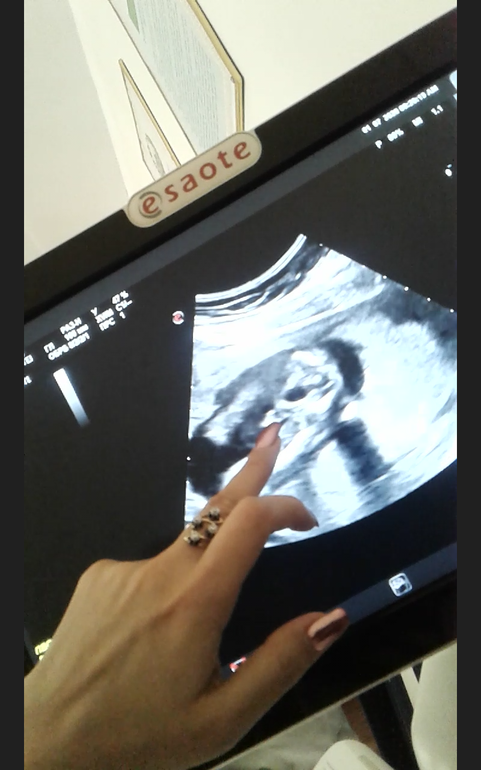

Это наш писюн 😆:

На последней , точно понятно. Снимала на видео, кадр только так смогла поймать.

))) прикольно ))) Дааа прям отчетливо так. До сегодняшнего дня то прятался , то тонус был. )))